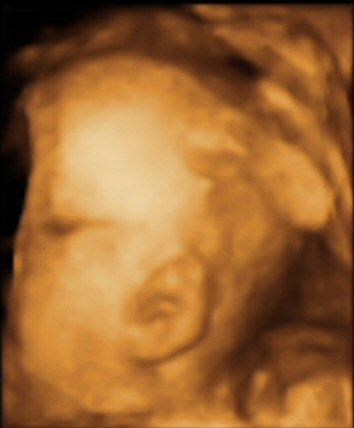

- The scan photos shown below are 3D images from the babybond 4D scan at 29 weeks gestation.